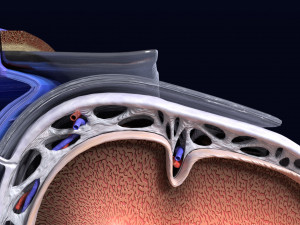

A blend model of brain along with its covering layers (meninges), skull bone and scalp labelled in detail and anatomically precise. The parts depicted are white, gray, pia, arachnoid, dura, bone, skin, fat, aponeurosis, periosteum, falx cerebri and more.

The material is high resolution image textures and normal maps based on non overlapping UVs. The texture and normal maps are packed with the blend file itself.